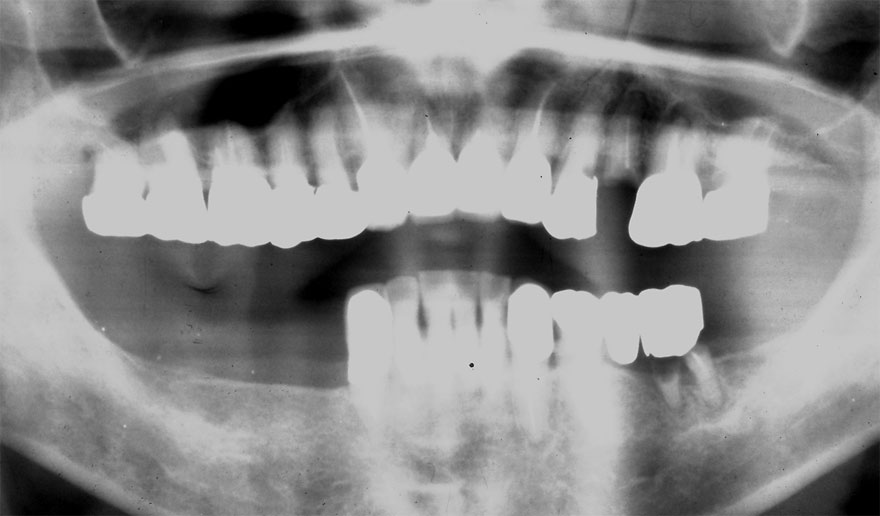

初診時 50歳 女性

22年後 72歳